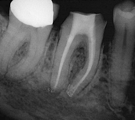

Long Term CaOH Cases

12 Month CaOH Treatment

14 Months CaOH Treatment

All Treatment performed by Dr. Brian A. Christopherson